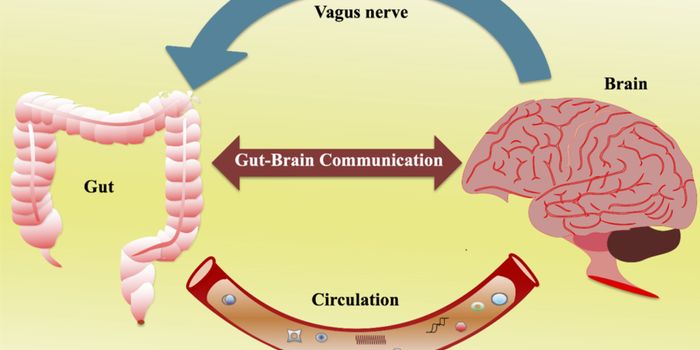

AUG 12, 2024NeuroscienceRecent advances in the field of microbiome research have provided valuable insights into the complex relationship betwee ...

AUG 11, 2024Clinical & Molecular DXThere are trillions of microorganisms in the human gut, many of which serve important functions. These microbes can help ...